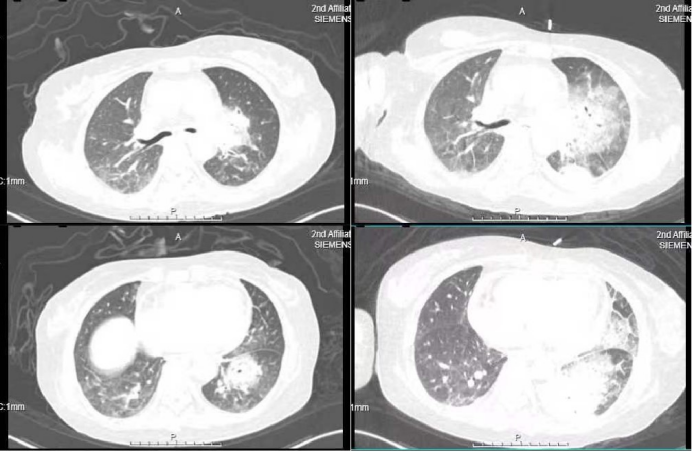

患者中年女性,农民,因“呼吸困难、咯血7天”于2023年9月7日入住我科。入院前7天,患者于我院内分泌科住院治疗时出现呼吸困难,伴咳嗽、咳痰,咳白色黏痰,痰中带血,呈鲜红色,病程中咯血量逐渐增多,每天10~20 ml,咯暗红色血性液体,伴发热,体温最高38.8℃。完善相关检查:血图分析提示白细胞计数15.21×109/L,CRP>200 mg/L,肺动脉CTA提示(图1):①肺动脉栓塞,累及左肺上叶前段、舌段,左肺下叶前内基底段局部受累可能;②左肺炎症较前明显增多。予哌拉西林舒巴坦、亚胺培南西司他丁、卡泊芬净抗感染,卡络磺、云南白药、矛头蝮蛇血凝酶止血后,咯血症状较前好转,余症状无明显改善,为求进一步诊疗于我科就诊。

图1  患者入院前肺动脉CTA